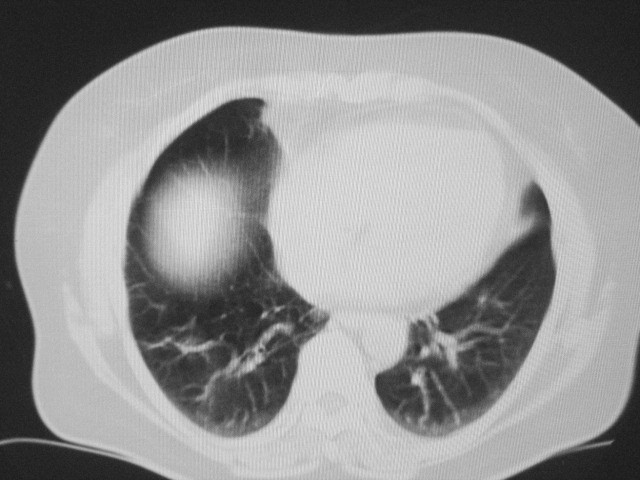

以下是引用清清楚楚在2007-8-28 7:13:00的发言:[br]右肺下叶可见斑片状高密度影,边缘模糊;右肺中叶内侧段及左肺舌段亦可见小斑片状模糊影。[br]考虑双肺感染,建议抗炎治疗后复查。

以下是引用天南地北在2007-8-27 23:49:00的发言:[br]右肺下叶可见斑片状高密度影,边缘模糊;右肺中叶内侧段及左肺舌段亦可见小斑片状模糊影。[br]考虑双肺感染,建议积极抗炎治疗后复查。

以下是引用天南地北在2007-8-27 23:49:00的发言:[br]右肺下叶可见斑片状高密度影,边缘模糊;右肺中叶内侧段及左肺舌段亦可见小斑片状模糊影。[br]考虑双肺感染,建议抗炎治疗后复查。

以下是引用难听在2007-8-28 13:17:00的发言:[br]右肺下叶背段支气管狭窄,是否可以考虑新生物伴阻塞性肺炎.请大家帮帮忙,这个病人是卫生局长的丈母娘.惹不起啊.